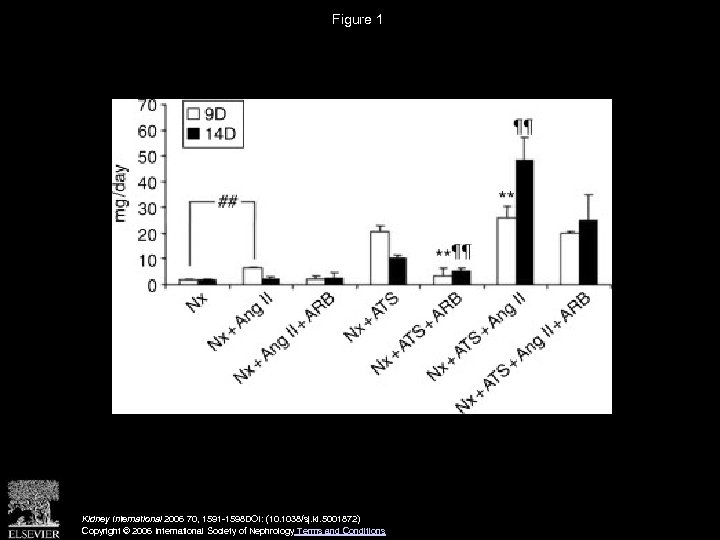

Figure 1 Kidney International 2006 70, 1591 -1598 DOI: (10. 1038/sj. ki. 5001872) Copyright © 2006 International Society of Nephrology Terms and Conditions